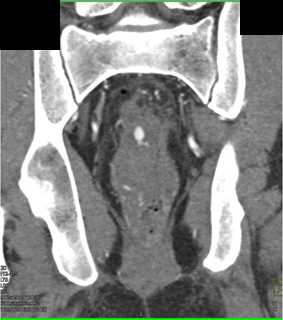

In this patient s/p GSW to the pelvis the best diagnosis is

active bleed in the rectum

foreign matter in pelvis

normal CTA with minimal bleed

spasm of vasculature